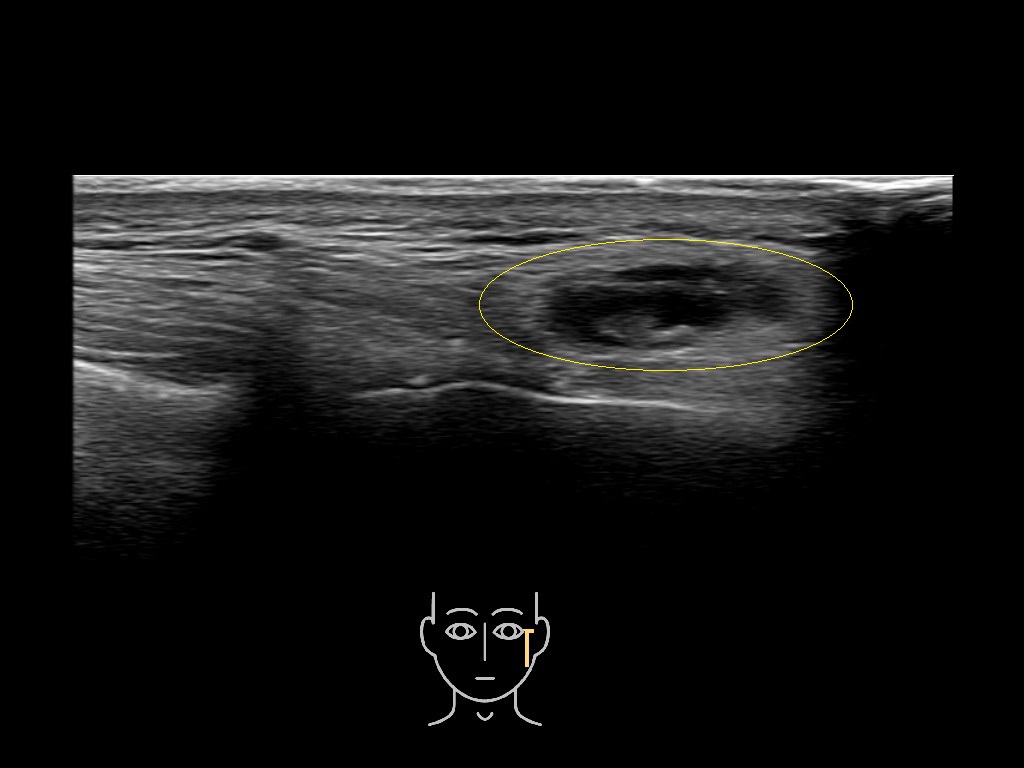

Filler injections in the parotid gland may go unnoticed, however, inflammatory reactions and abscesses may occur. Hypervascularity can be seen with color doppler. Filler deposits are supposed to be injected into the superficial fatty layer . The space to inject into this layer may be limited. Routinely we measure a width of 2-4 millimeters with sometimes subcutaneous layers being less than one millimeter thick.

Study the first image to recognize the different layers. If you are sure about the layers, swipe to the second image to view the answer (if applicable).